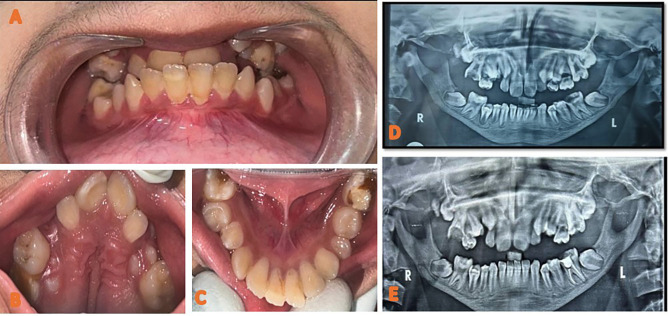

Pyknodysostosis (PKND),也被称为Toulouse-Lautrec综合征,是一种罕见的常染色体隐性遗传病,其特征是四肢短小、身材矮小和广泛性骨质硬化。这种疾病的标志性症状包括末段指骨硬化、持续的囟门、延迟缝合闭合、虫状骨、额窦缺失、下颌角钝角和相对下颌前突。这个病例报告阐述了一个13岁男孩的全身性特征,如身材矮小,前额和顶骨隆起,鼻梁凹陷,鹰嘴鼻,中脸发育不全,指尖皮肤起皱,指甲异常。口腔齿科表现为上颌深腭、腭襞突出、上颌弓狭窄、上颌前牙前倾、III类骨骼轮廓。x线表现为鼻窦发育不全,下颌骨萎缩,牛牙畸形,恒牙阻生,乳牙保留数颗。本病例强调了在识别PKND的牙齿和全身体征时需要保持警惕,强调了早期诊断和量身定制的治疗策略对改善患者预后的重要性。关键词:收缩性口瘘,图卢兹-劳特雷克综合征,口腔管理

Pyknodysostosis (PKND), also referred to as Toulouse-Lautrec Syndrome, is a rare autosomal recessive disorder marked by short limbs, short stature, and generalized bone sclerosis. The hallmark signs of this disorder include sclerosis of the terminal phalanges, persistent fontanelles, delayed suture closure, wormian bones, absence of frontal sinuses, obtuse mandibular gonial angle, and relative mandibular prognathism. This case report elucidates a 13-year-old boy presenting with systemic features such as short stature, frontal and parietal bossing, depressed nasal bridge, a beaked nose, hypoplastic midface, wrinkled skin on the fingertips, and nail abnormalities. The oro-dental manifestations include deep palate, prominent palatal rugae, constricted maxillary arch, proclined maxillary anterior teeth and Class III skeletal profile. Radiographic findings showed hypoplastic paranasal sinuses, atrophic mandible, taurodontism, impacted permanent teeth along with several retained deciduous molars. This case highlights the need for vigilance in identifying the dental and systemic signs of PKND, emphasizing the importance of early diagnosis and tailored treatment strategies to improve patient outcomes. Key words:Pyknodysostosis, Toulouse-Lautrec syndrome, Dental management.